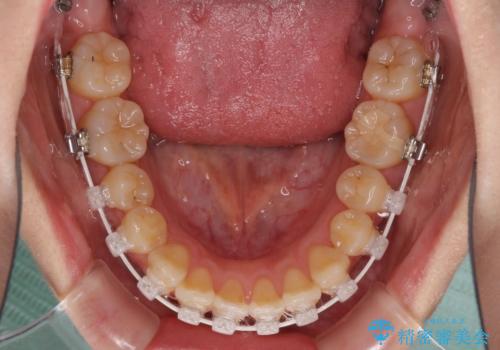

ハーフリンガル 反対咬合の改善

- ハーフリンガル

目立ちにくい装置での治療をご希望とのことで、上顎が裏側装置、下顎が表側装置のハーフリンガルにより矯正治療を行うこととしました。

下顎の歯列全体を後方に動かす場合、さまざまリスクを伴うため慎重に行う必要があり、さらには移動量に限界があるため、治療計画は無理のないものとしなければなりません。

下顎左右の奥にアンカーボルトを使用して、無理のない範囲で後方に移動させ、きれいに仕上げることができました。